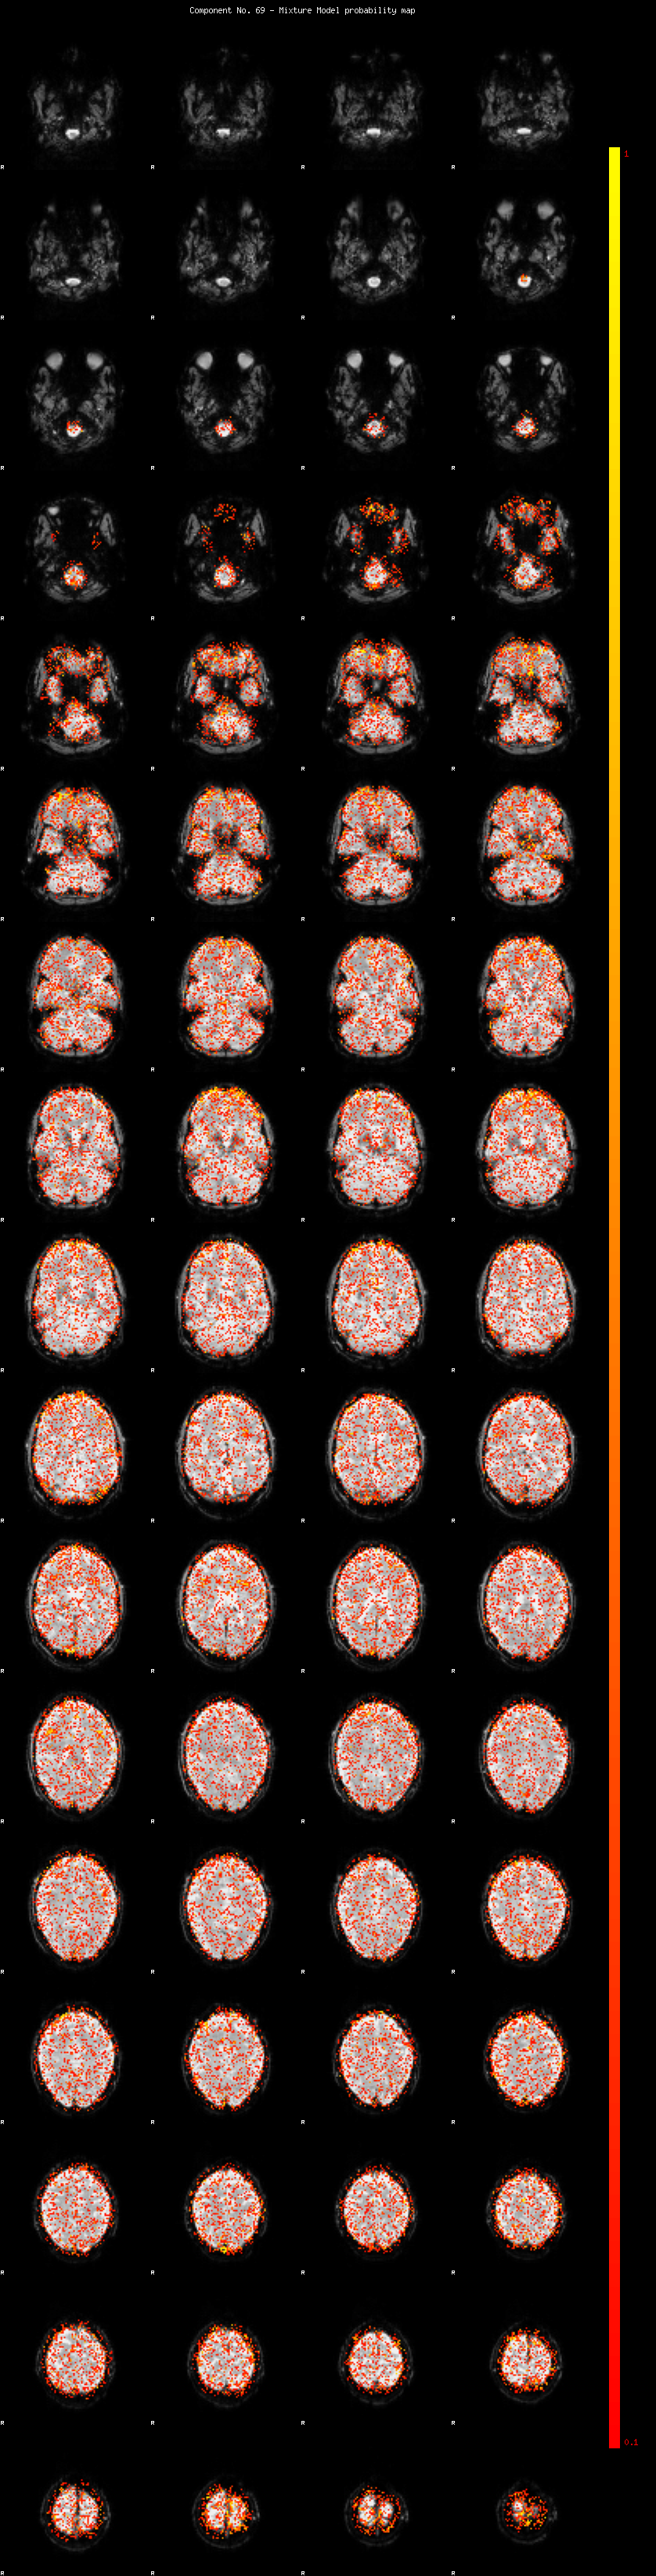

IC_69 Mixture Model fit

Means : -0.000000 2.035350 -2.051938

Vars : 1.000000 0.712266 0.735757

Prop. : 0.910897 0.038995 0.050108